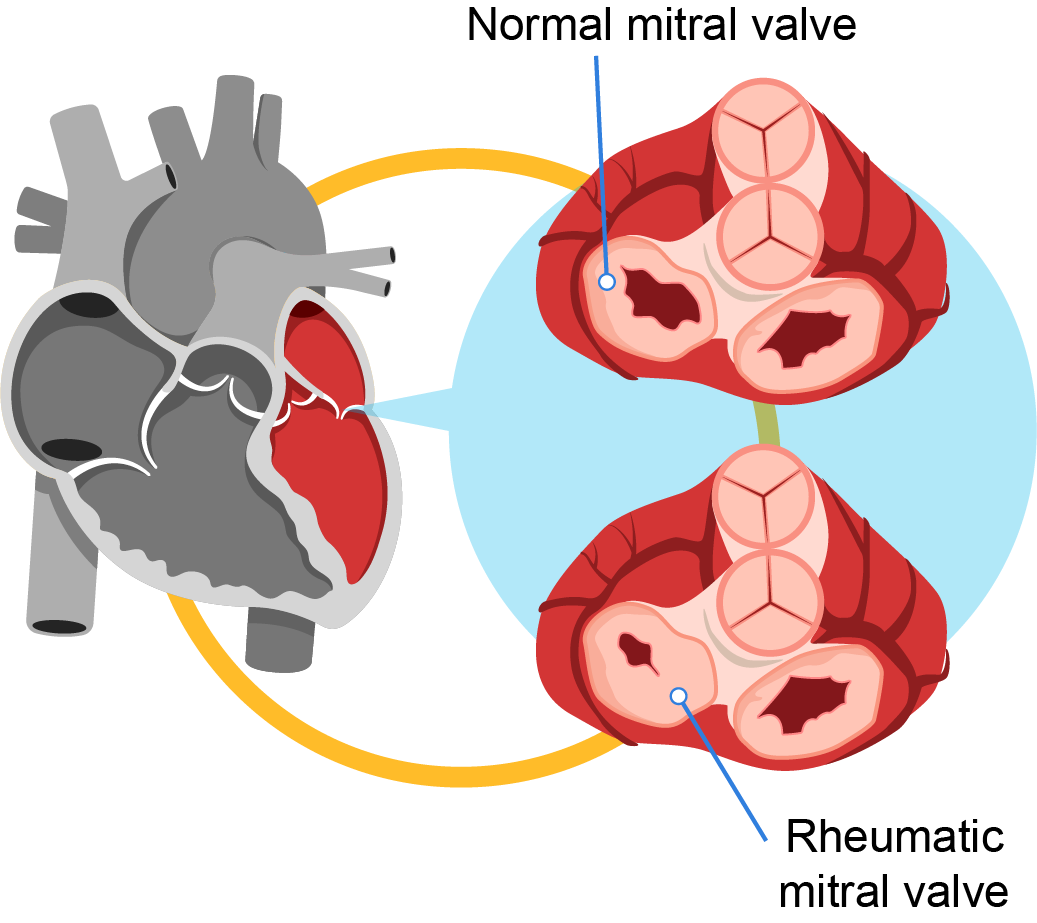

RHEUMATIC HEART DISEASE Define Etiology Risk Diagnostic

Rheumatic Fever And Rheumatic Heart Disease

Rheumatic Fever And Rheumatic Heart Disease